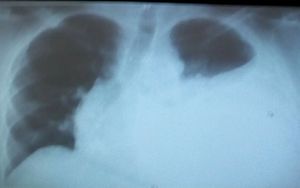

What do you think the patology Is? Anda Why?

Left pleural effusion

It looks like “White Chest”